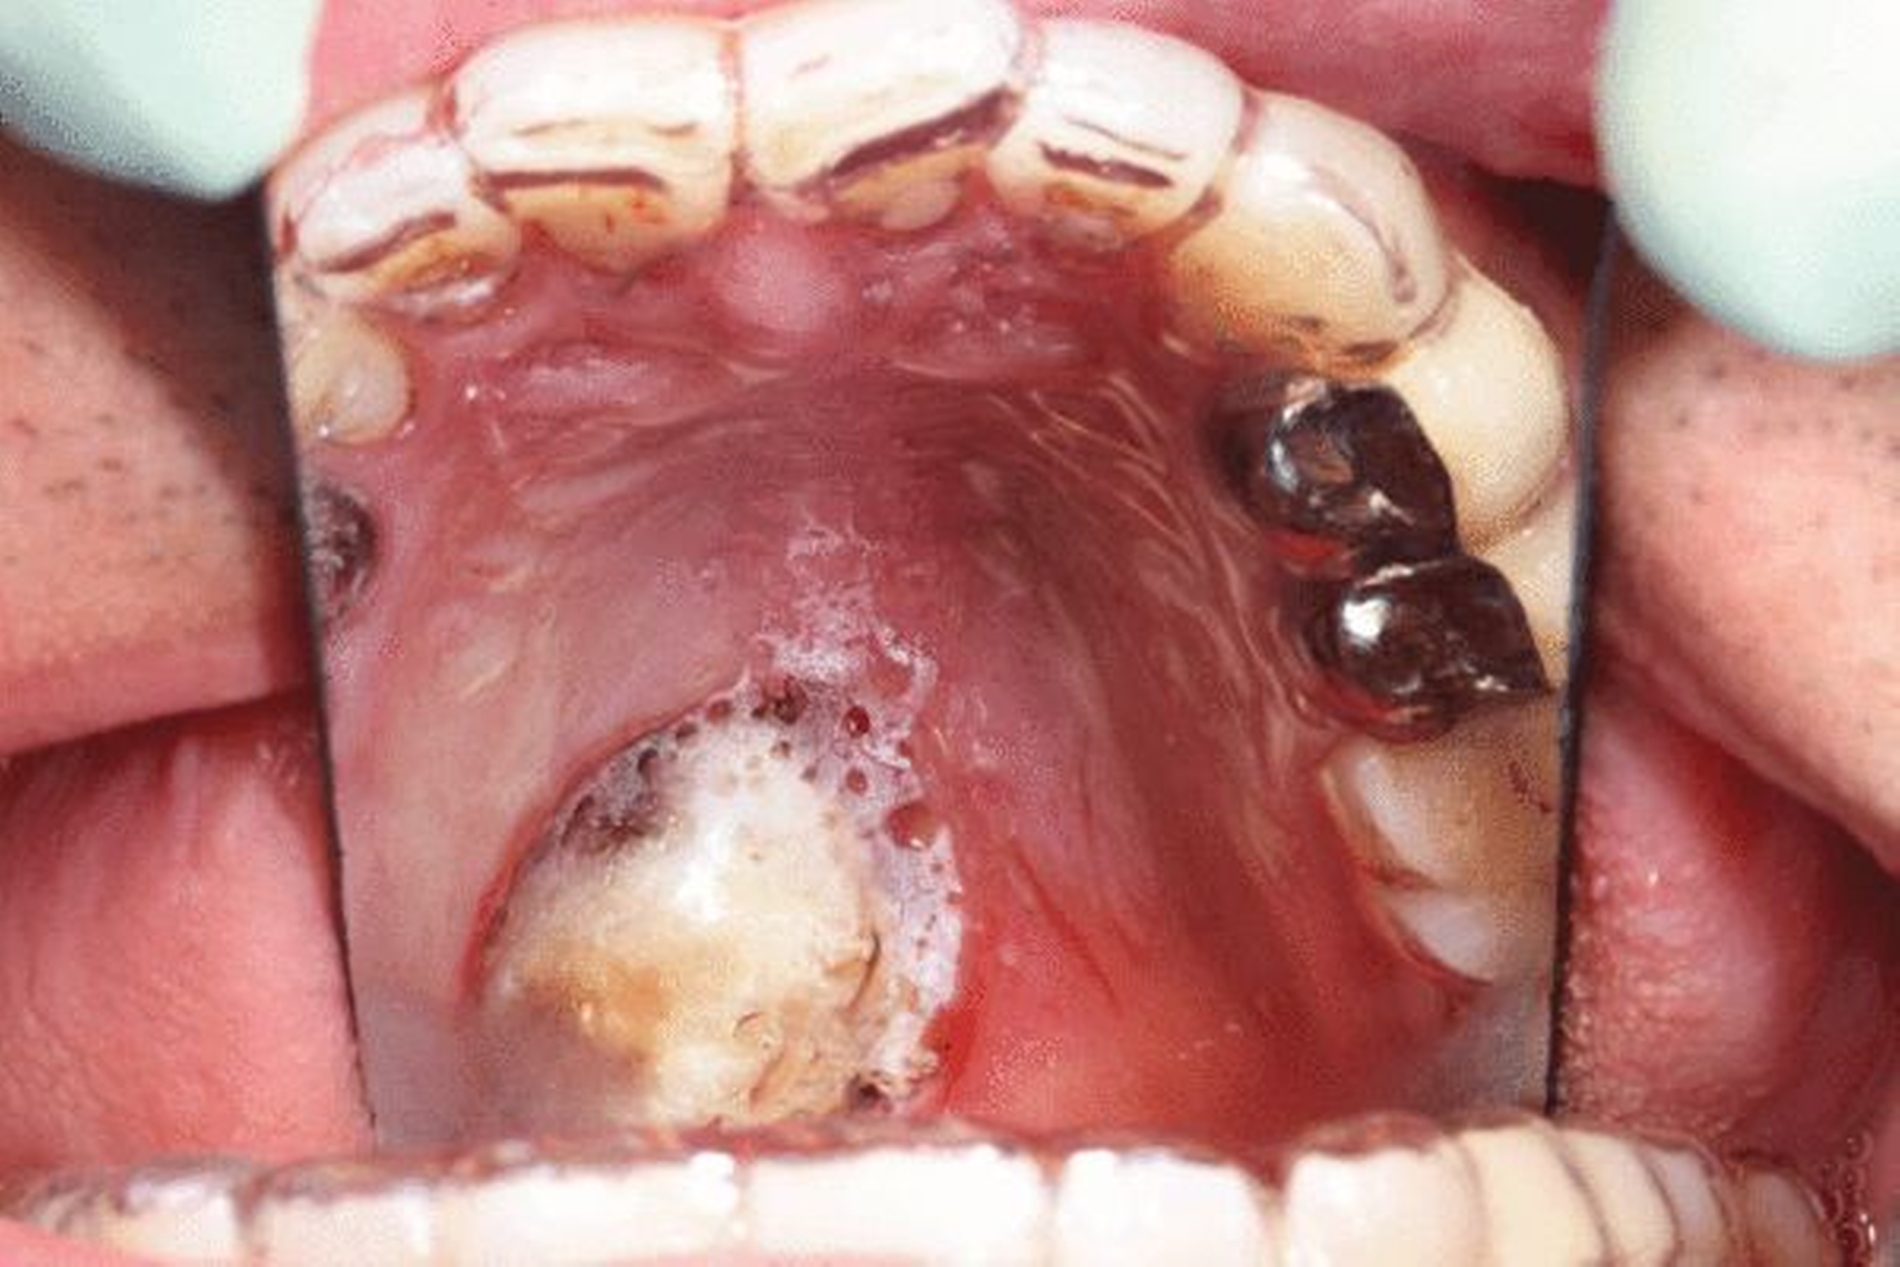

Klinisch stellte sich eine symptomlose, am Übergang vom Palatum durum zum Palatum molle linksseitig gelegene, circa 1 cm große, runde, klar begrenzte, weiche, nicht druckdolente Erhebung dar (Abbildung 1).

Da eine sekundäre Granulation des Defekts intendiert war, wurde die Wunde zuerst zur Blutungsprophylaxe mit einer Cellulose-Tamponade und einem Tranexamsäuregel versorgt. Anschließend wurde als Druckverband und Wundschutz eine Verbandsplatte eingegliedert (Abbildungen 4 und 5). Die histopathologische Aufarbeitung des entnommenen Präparats ergab ein mit Plattenepithel bedecktes Weichteil- und Drüsengewebe mit Manifestationen einer zystischen, regressiv veränderten epithelialen Läsion, das mit dem klinisch bekannten Steatozystom vereinbar ist. In den Nachsorgeuntersuchungen im Intervall von drei Monaten zeigte sich eine zeitgerechte Wundheilung mit vollständiger Restitutio ad integrum ohne Anhalt für ein Rezidiv.